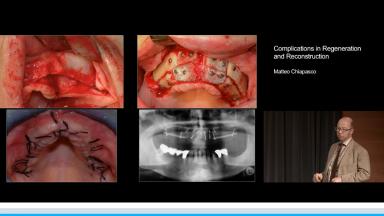

Complications in Regeneration and Reconstruction

Matteo Chiapasco

This lecture reviews in detail the various defects encountered in clinical practice that may need regenerative procedures for hard and soft tissue augmentation. The presentation is supported with excellent visual aids that illustrate how these defects can be reconstructed for prosthodontically driven implant placement. It also addresses how to prevent complications in regenerative and reconstruction procedures as well as the predominant treatment options to manage these complications. Clinical outcomes are supported by reference to several studies and clinical recommendations from the 4th ITI Consensus Conference.